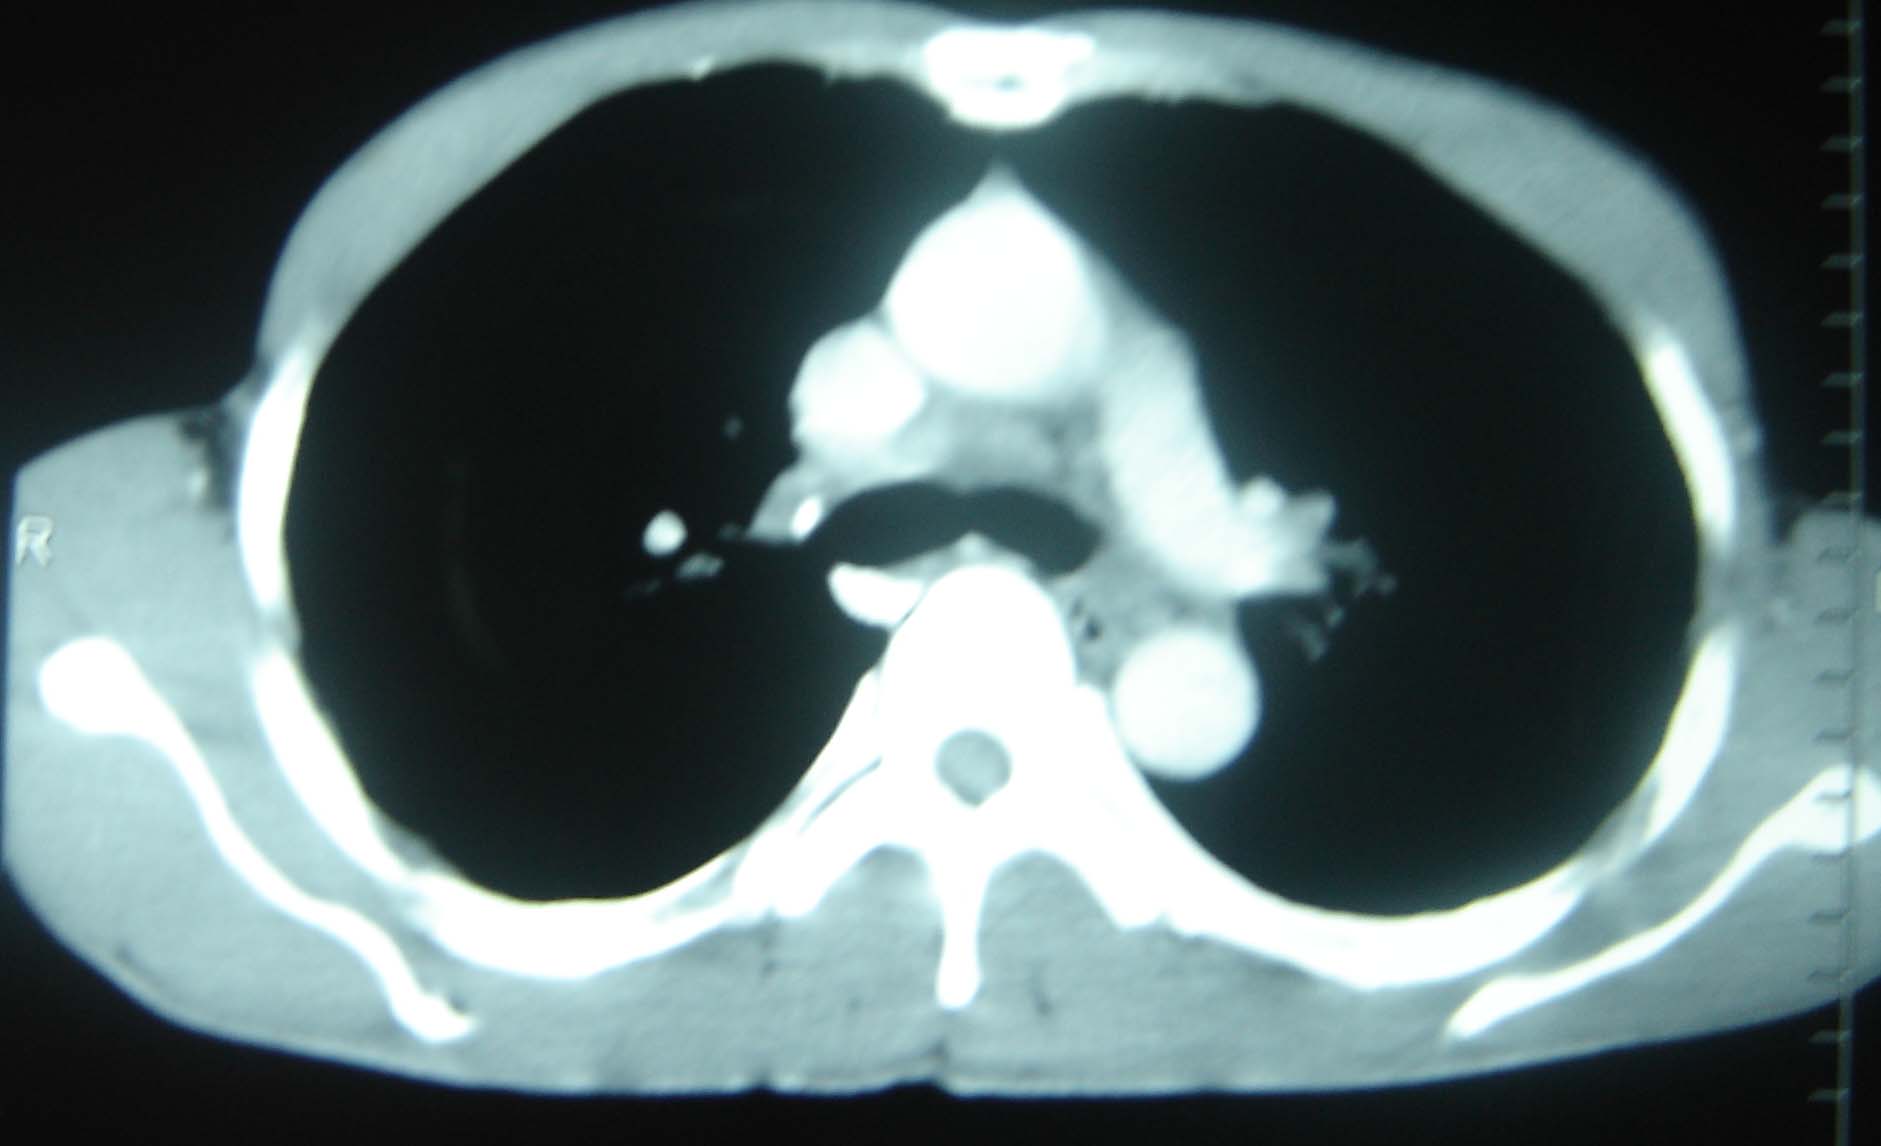

标题: CT25321:两肺多发结节 请会诊 [打印本页]

标题: CT25321:两肺多发结节 请会诊

男 、43岁,咳嗽胸痛,装修工,平时接触粉尘较多,有吸烟史10多年,纤维支气管镜检查未发现异常,胃镜、腹部b超检查亦未发现异常,颈部淋巴结活检未发现肿瘤细胞。